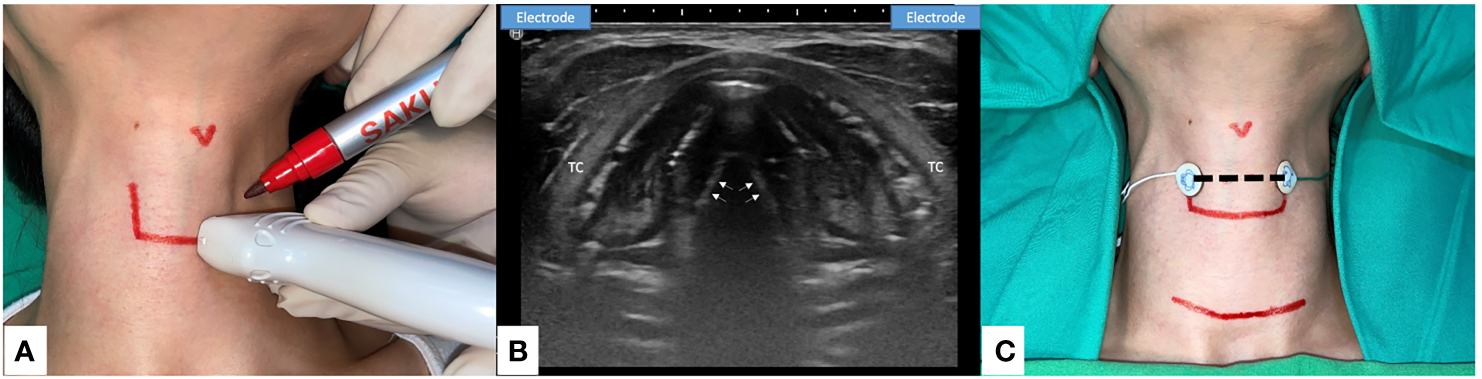

Figure 3

Transcutaneous Anterior Laryngeal Recording electrode placement for Intraoperative neural monitoring. (A) Preoperative skin marking: lateral border of thyroid cartilage and the level of true vocal fold. Precise localization may be done with the application of ultrasound (US). (B) The axial view of true vocal folds (white arrow). Lateral side of the thyroid cartilage (TC) lamina is the optimal location to place the skin surface electrodes (US illustration). (C) Transcutaneous recording electrodes are placed at the level of true vocal fold (dotted line). Transcutaneous recording method is applicable in small incision wound or remote thyroid surgery. Skin flap beneath the surface electrodes should be avoided.